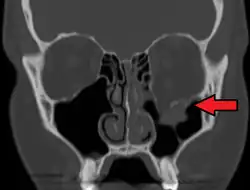

Left orbital floor fracture

Radiography, imaging of tissues using X-rays, is used to rule out facial fractures.[2] Angiography (X-rays taken of the inside of blood vessels) can be used to locate the source of bleeding.[11] However the complex bones and tissues of the face can make it difficult to interpret plain radiographs; CT scanning is better for detecting fractures and examining soft tissues, and is often needed to determine whether surgery is necessary, but it is more expensive and difficult to obtain.[4] CT scanning is usually considered to be more definitive and better at detecting facial injuries than X-ray.[3] CT scanning is especially likely to be used in people with multiple injuries who need CT scans to assess for other injuries anyway.[12]